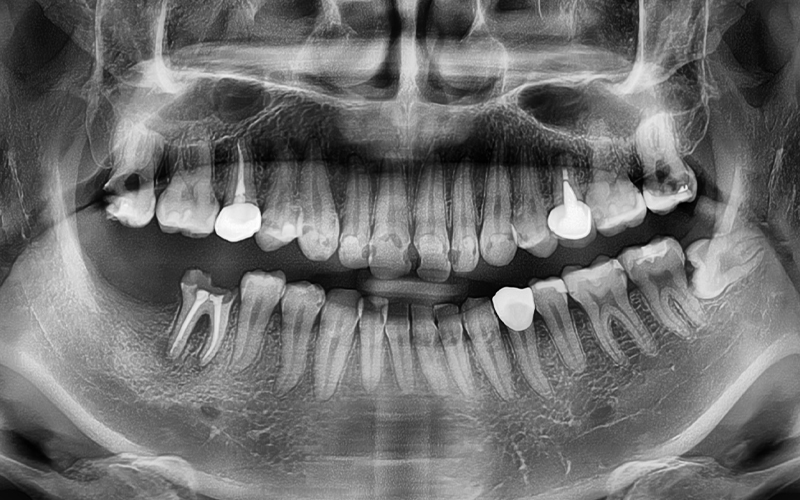

The patient we are introducing had several cavities in progress,

and the pain would come and go,

which made it even easier to miss the right timing for treatment.

As can actually be seen in the treatment record,

more than 10 teeth received

root canal treatment,

and most were accompanied by complex inflammation and nerve infection.

In particular, treatment was carried out across a wide area,

including the upper front teeth and molars.

A panoramic X-ray was taken

to perform a detailed check,

and an overall treatment plan was established.